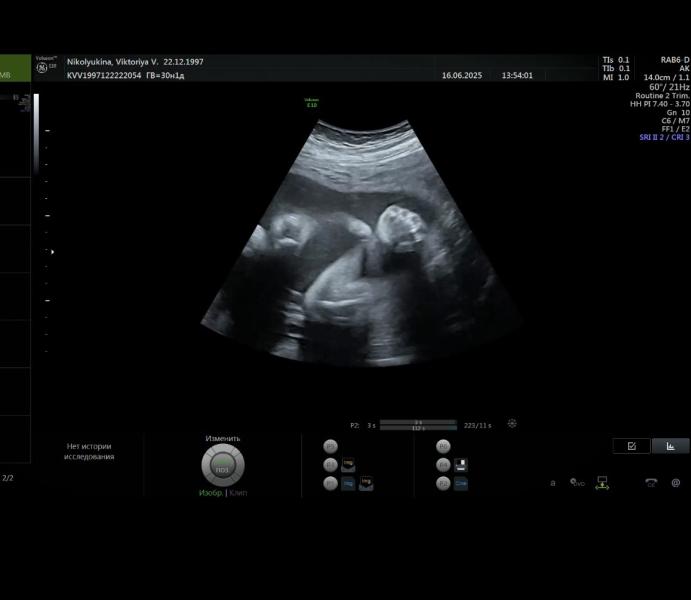

Сдаем анализы, посещаем врачей. Сегодня была на УЗИ)

Малышка лежит головкой вниз, как всегда идет по сроку, 30,1 недель. Вес у нас 1609 🥰

По размеру косточек сказали, что наверно ростом в папу будем, длинные 😄

Доча лежала неудобно, опять не смогли нормально посмотреть на нее. Но зато она показала свои губки пухлые с носиком , и ручку с кулачком 😄💪🏼